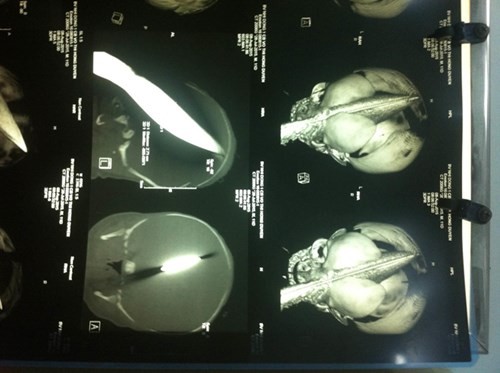

Ngay lập tức cháu bé được tiến hành truyền dịch, làm các xét nghiệm chẩn đoán hình ảnh. Kết quả chụp CT cho thấy bé bị dao đâm từ hốc mắt trái xuyên qua não phải, thấu ra tận phía sau.

Hình ảnh con dao bầu cắm sâu vào sọ cháu bé. |

Con dao bầu lấy ra khỏi đầu cháu bé dài 28cm, rộng 2,7cm và phần dao đâm ngập vào trán sâu tới 11cm.